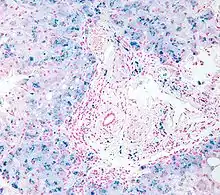

In histology, histopathology, and clinical pathology, Perls Prussian blue is a commonly used method to detect the presence of iron in tissue or cell samples.[1]: 235 [2][3][4] Perls Prussian Blue derives its name from the German pathologist Max Perls (1843–1881), who described the technique in 1867.[2] The method does not involve the application of a dye, but rather causes the pigment Prussian blue to form directly within the tissue.[5] The method stains mostly iron in the ferric state which includes ferritin and hemosiderin, rather than iron in the ferrous state.[6]

Perls's method is used to indicate "non-heme" iron in tissues such as ferritin and hemosiderin,[6] the procedure does not stain iron that is bound to porphyrin forming heme such as hemoglobin and myoglobin.[2] The stain is an important histochemical stain used to demonstrate the distribution and amount of iron deposits in liver tissue, often in the form of a biopsy.[6][7] Perls's procedure may be used to identify excess iron deposits such as hemosiderin deposits (hemosiderosis) and in conditions such as hereditary hemochromatosis.[8] Perls Prussian blue is commonly used on bone marrow aspirates to indicate levels of iron storage[4] and may provide reliable evidence of iron deficiency.[7]

Perls did not publish a detailed procedure other than indicating a dilute potassium ferrocyanide solution was applied to the tissue followed by hydrochloric acid.[2] Ferric iron deposits in tissue (present mostly as ferric iron within the storage protein ferritin) then react with the soluble ferrocyanide in the stain to form the insoluble Prussian blue pigment (a complex hydrated ferric ferrocyanide substance). These deposits are then visualizable microscopically as blue or purple deposits.[9]

Many methods of performing Perls Prussian blue stain for iron have been published, [2] Drury and Wallington (1980) give a protocol that uses a mixture of 1 part 2% hydrochloric acid and 1 part 2% potassium ferrocyanide that is applied to the section for 20–30 minutes followed by a rinse in distilled water and application of a counterstain such as eosin, safranin or neutral red.[5]